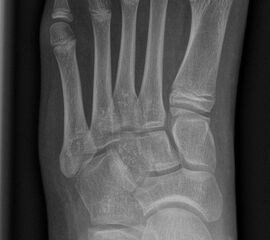

Abb.1 a-b: Beispiel einer noch offenen Wachstumsfuge im dorsalen Bereich des Calcaneus: (a) Alter 6 und (b) Alter 9 Jahre.

In der Regel bestehen aktive Wachstumsfugen bei Mädchen bis zum 12. und bei Jungen bis zum 14. Lebensjahr, mit Abweichungen von einem Jahr nach unten und nach oben. Präzise Informationen unter anderem darüber gibt das präoperative Röntgenbild (Abb. 2).

Abb. 2 a-c: offene Wachstumsfugen MT I Basis und Zehen (a), teilweise geöffnete Wachstumsfugen (b) und geschlossene Wachstumsfugen (c).